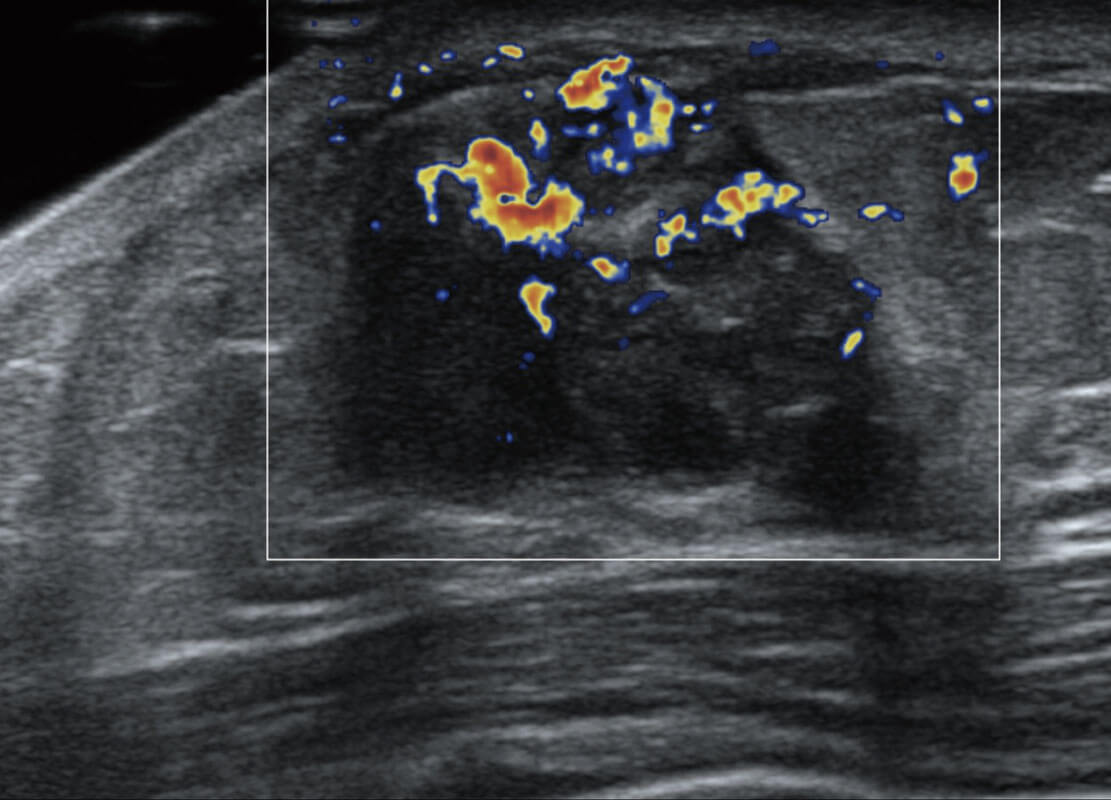

乳腺超声 / 新生儿

P60搭载宽频带线阵探头、宽景成像、弹性成像技术,为您提供乳腺全面应用方案。P60支持高频相控阵探头、线阵探头、腹部高频探头、腹部微凸探头等,丰富的探头群搭载敏感的彩色血流成像,适用于新生儿多种脏器检测要求,满足新生儿筛查需求。

• 乳腺导管癌

• 乳腺癌显微血流